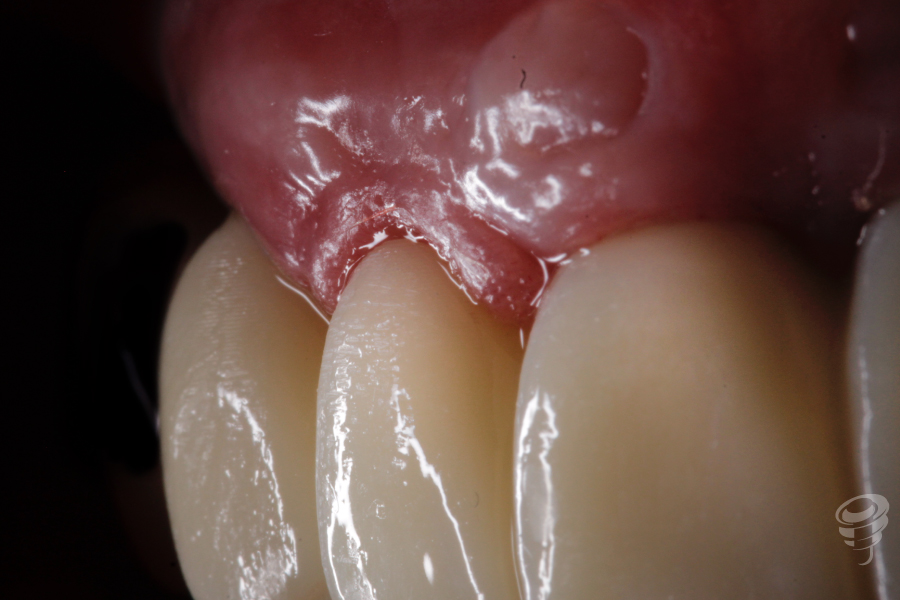

4 meses post cirugía

4 meses post cirugía observamos tejidos blandos relativamente estables.

La prótesis queda sobrecontorneada debido al posicionamiento periimplantario de los tejidos blandos.